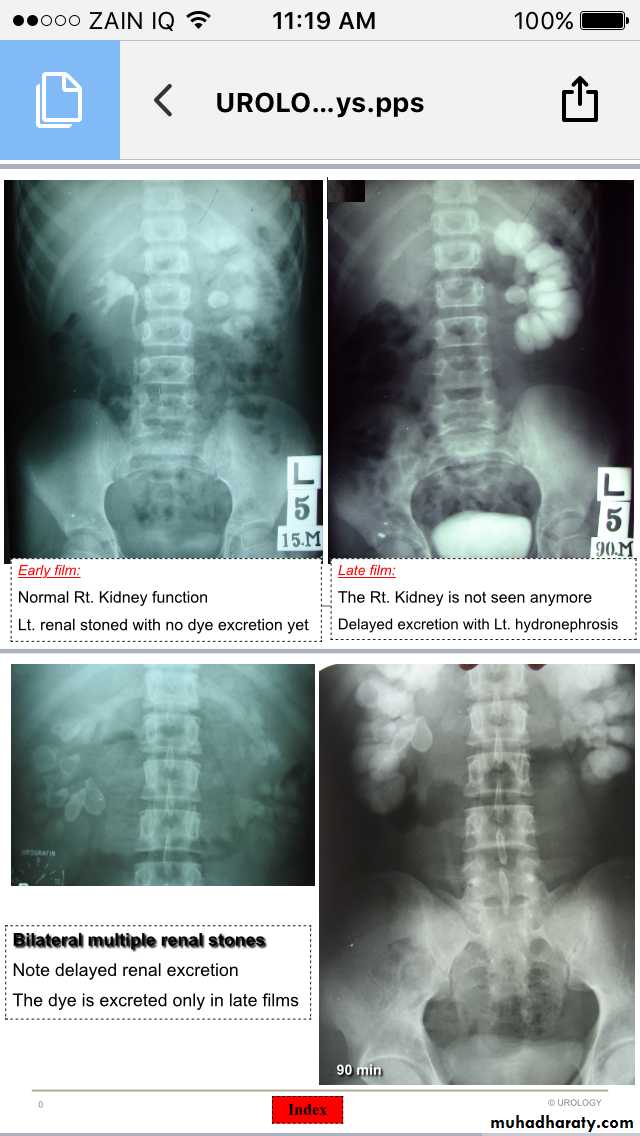

IVU

Renal stones

Ureteric stones

Hydronephrosis-Hydroureter